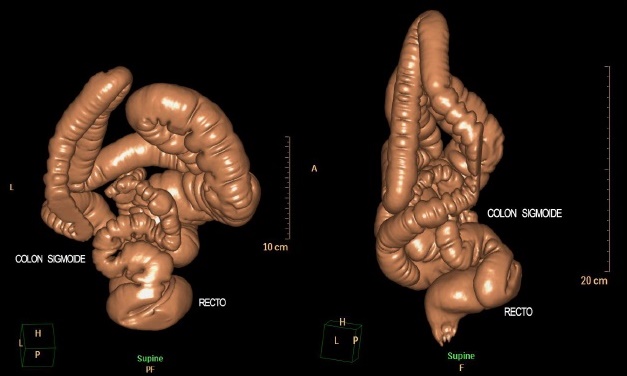

Una vez que se evaluó la paciente en consulta preoperatoria y ante la duda diagnostica, se realizó tomografía de abdomen/pelvis y protocolo de colonoscopia virtual con PPIT en el que se observó colon extremadamente redundante, con longitud aproximada de 171.7 cm (Figura 5), presencia de 12 curvas en su trayecto y finalmente, se confirmó la ausencia de divertículo gigante en el sigmoide (Figura 6, 7, 8A y 8B).

Figura 8A y 8B Caso 2: vista posterosuperior (A) y lateral izquierda (B) de imagen volumétrica de todos los segmentos colónicos en posición supina. Se confirma la redundancia excepcional del colon sobre todo en su porción sigmoidea.

La extrema redundancia del colon, y en especial del sigmoides, lo cual aunado a la distensión de esa área colónica dada por la ingesta de alimentos formadores de gases, así como la complexión de la paciente, (caracterizada por escaso panículo adiposo abdominal ), explico el dolor y la presencia de la “tumoración” abdominal. Se recomendó a la paciente establecer la relación, mediante un diario, de los alimentos con el dolor y la distensión abdominal.